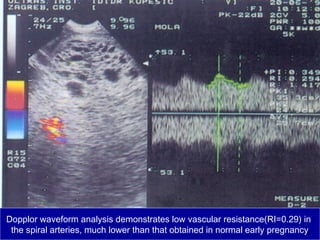

Dopplor waveform analysis demonstrates low vascular resistance(RI=0.29) in

the spiral arteries, much lower than that obtained in normal early pregnancy